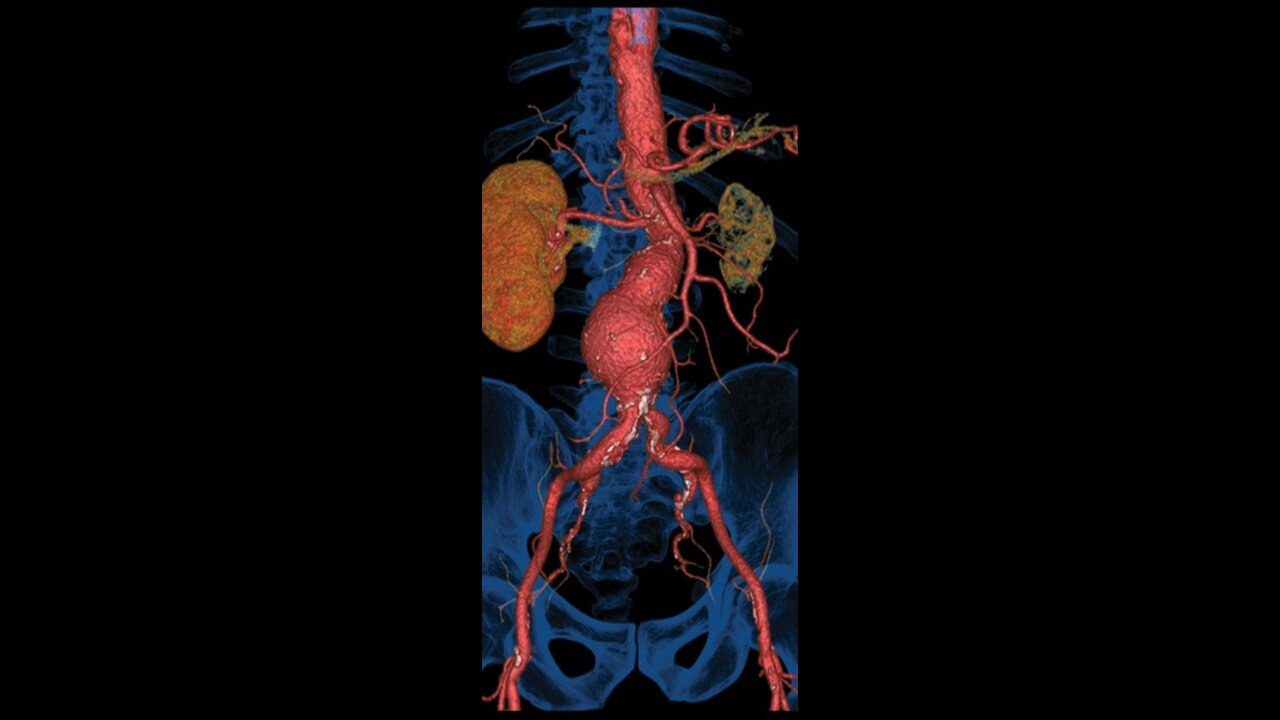

ΑΞΟΝΙΚΟΣ ΤΟΜΟΓΡΑΦΟΣ

Ο υπερσύγχρονος αξονικός τομογράφος Revolution Maxima του αμερικανικού οίκου General Electric Healthcare, με ανιχνευτή 128 τομών αποτελεί ένα σημαντικό άλμα προόδου στη διαγνωστική απεικόνιση και πλέον είναι διαθέσιμος στην κλινική μας. Ο Revolution Maxima της GE ανταποκρίνεται σε ένα ευρύ φάσμα κλινικών εφαρμογών, από την επείγουσα ιατρική και την ογκολογία έως τις προληπτικές εξετάσεις ρουτίνας.

- Αξονική αγγειογραφία

Απεικόνιση εξαιρετικής ποιότητας

Ανιχνευτές προηγμένης τεχνολογίας που δημιουργούν εξαιρετικά λεπτές

τομές, με πολύ υψηλή χωρική ανάλυση.